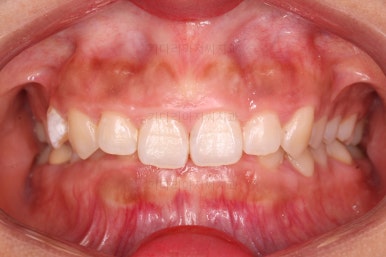

초진 시 얼굴모습이에요.

아무래도 옥니로 인해서 웃거나 말할 때 앞니가 어두워보이고 잇몸이 많아 보이시네요.

옆라인에서 입은 튀어나온 느낌은 없지만 턱끝만 살짝 볼륨감이 있는 편이었어요.

그렇다고 주걱턱은 아닙니다.